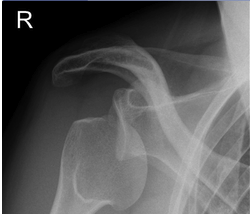

What is shown on this X-ray?